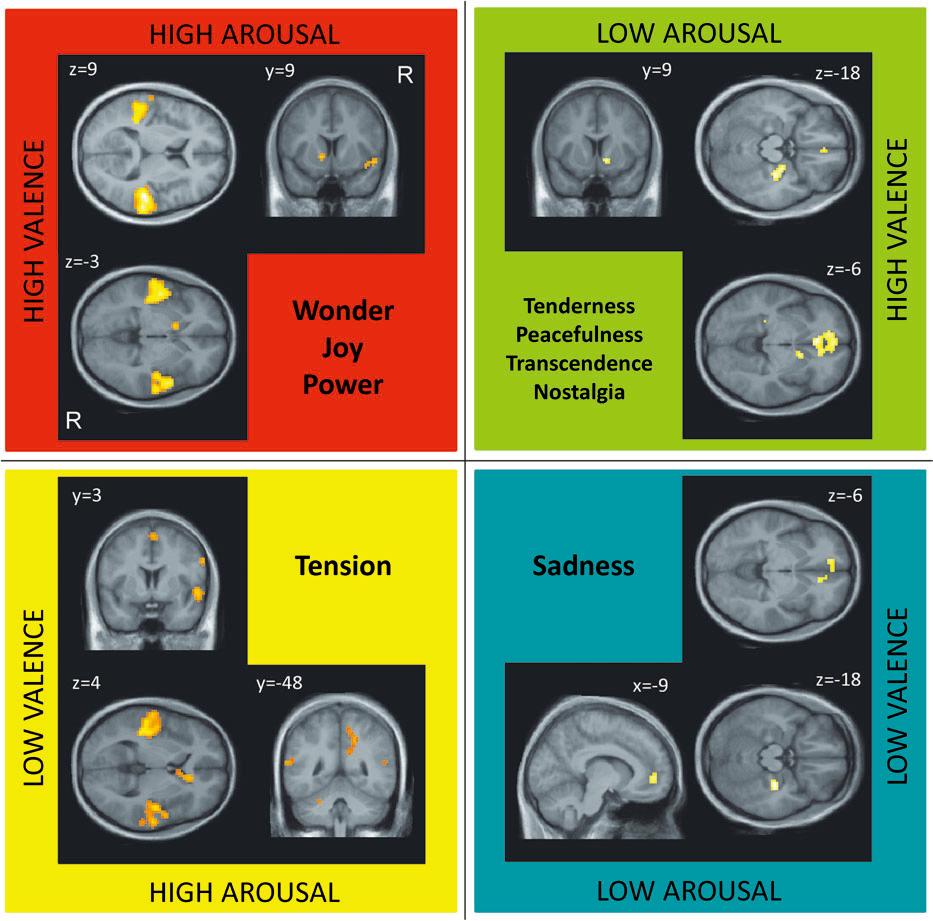

結果顯示,實驗參與者對於音樂的評分和實驗者的認定是一致的(例如實驗者定義為平靜的音樂,實驗參與者在平靜這個項目的評分也是最高的)。除此之外,也可以根據音樂誘發的興奮程度(arousal)及評價(valence)將所有類型分成四類。這四種不同類型的音樂分別會誘發不同腦部區域的活化。簡單來說,正向的音樂會誘發先前研究就已證實與獎賞有關的區域(striatum, insula),但因為興奮程度的不同,會有不一樣的活化型態。再者,只要是高興奮程度的音樂類型都會誘發知覺運動區域的活化;低興奮程度的音樂類型則會誘發與記憶( hippocampus)以及自我(ventral medial prefrontal cortex)有關係的區域。